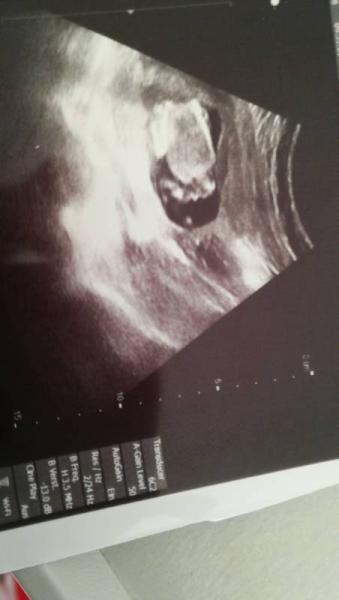

Das soll eventuell das Geschlecht verraten, könnt ihr es erkennen ?

Du meinst wahrscheinlich die kleine Ausbuchtung am pobbes. Bei meinem US in Krankenhaus hat sie auch nach dem Geschlecht gesucht auch dann von hinten und meinte nur, sie würde keine Hoden finden. Weswegen ich bei dir davon ausgehe dies könnten Hoden sein. Denn bei meinem US sah man null außer die Post backen

Sieht aus wie Junge

Junge;-) sah bei mir nun zweimal genauso aus. Ggf wölbt sich bei Mädels auch das Geschlecht etwas vor aber das sieht eindeutig zu „zipfelig“ für meine Begriffe aus